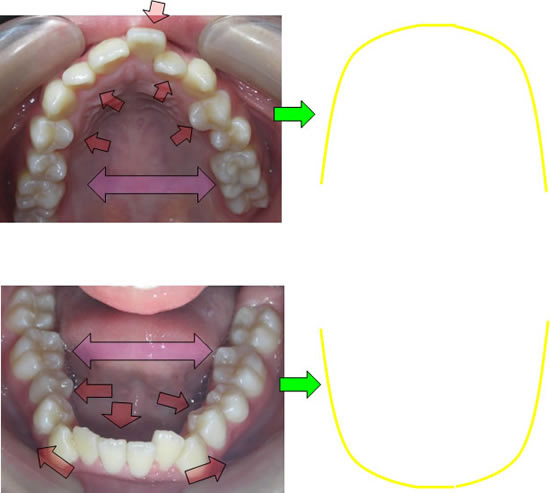

本来、この方が本来成長するはずであったところは上記のような上下顎のイメージになります!

顎が成長して(咀嚼や周囲の筋肉の調和などにより)歯が並ぶのに十分なスペースができさえすれば、乱れて生えてきた歯は自然に本来その歯が並ぶべき位置まで動いていってくれるという発想です。

SH療法の特徴

顎が小さいものは、歯を顎のサイズ合わせて歯を並べていく。

歯を抜いて数を減らすことにより、スペースを作り並べていく。

という発想が一般的な矯正治療の考え方です。

SH療法は本来成長するはずであったところまで誘導(成長)していくという発想です。

歯を並べるのは、あなた方自身の生体で歯自身が居心地の良い場所へ動いていくという発想です。(また、装置を外している時間の方が長く、正しい咀嚼、姿勢などが大変重要になります)